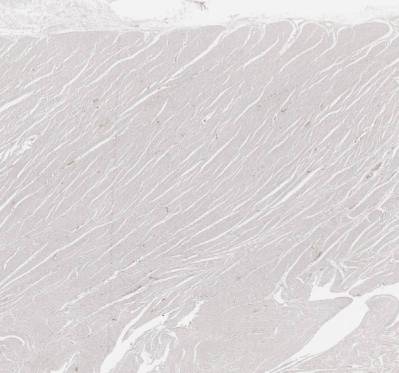

A86 Prostatahyperplasie

Verbreiterung der glatten Muskulatur und des Stromas